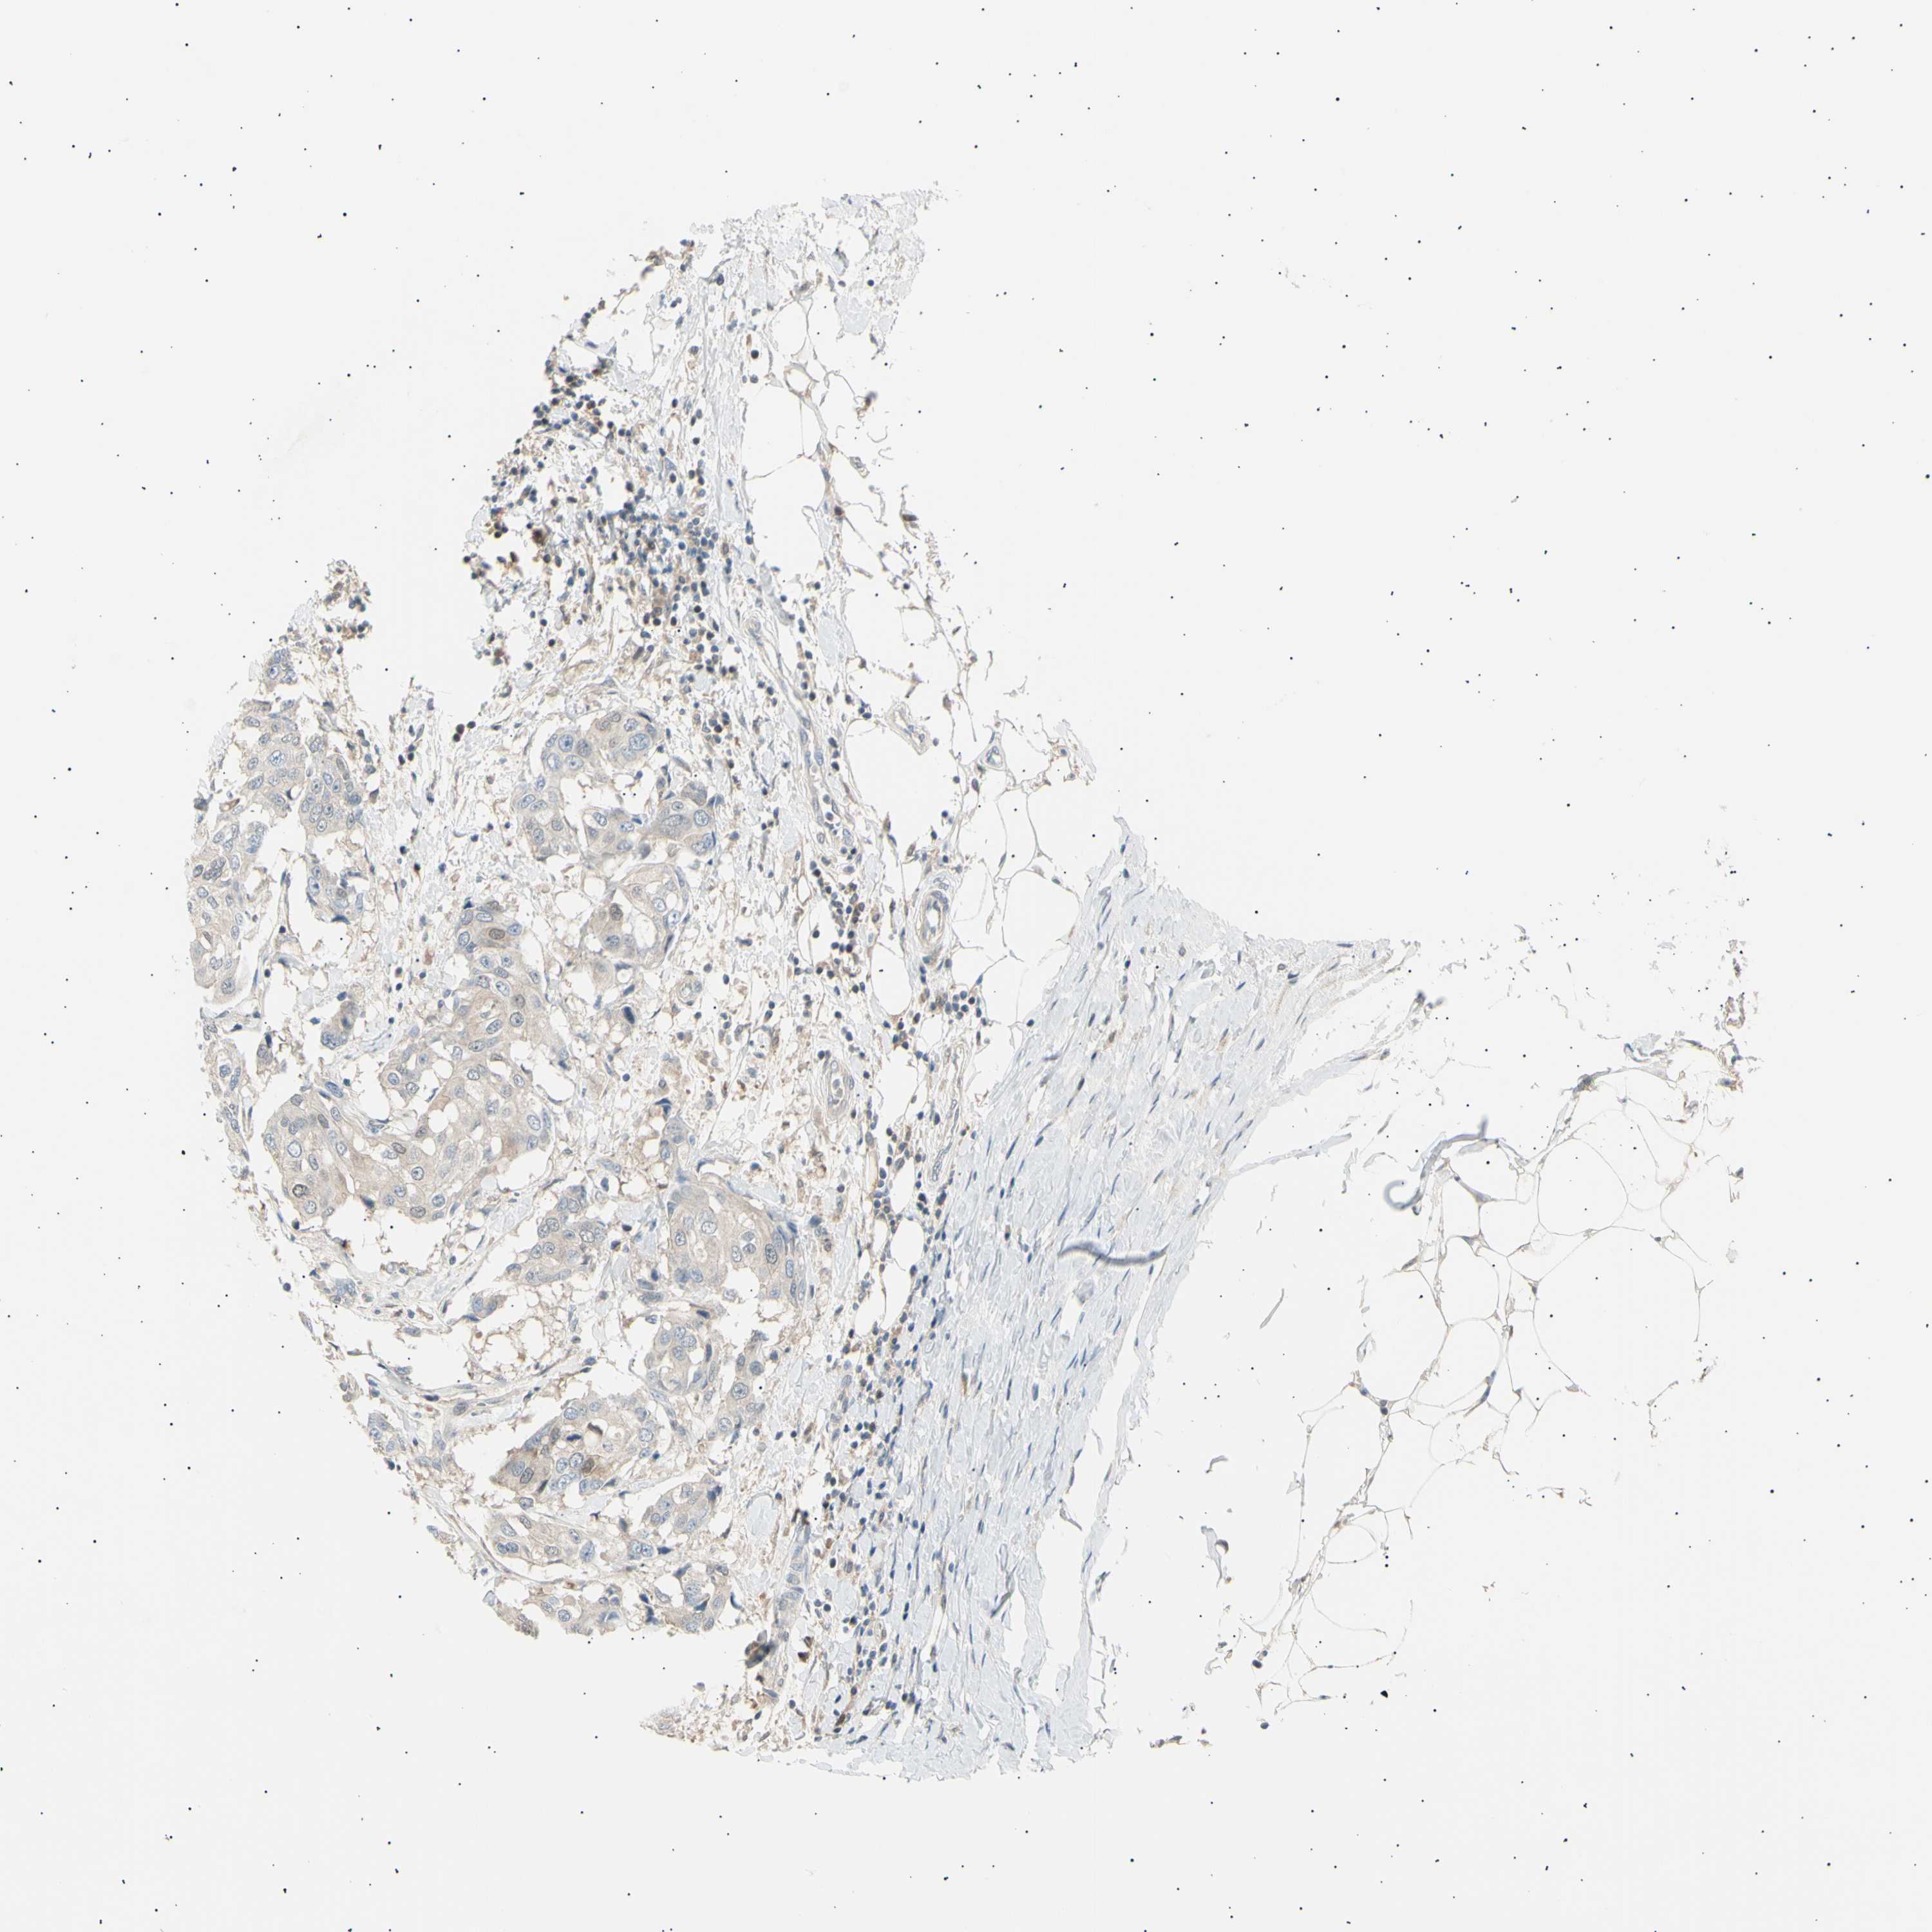

CANCER BREAST CANCER Show tissue menu

BRCA TCGA BRCA VALIDATION PROTEIN EXPRESSION